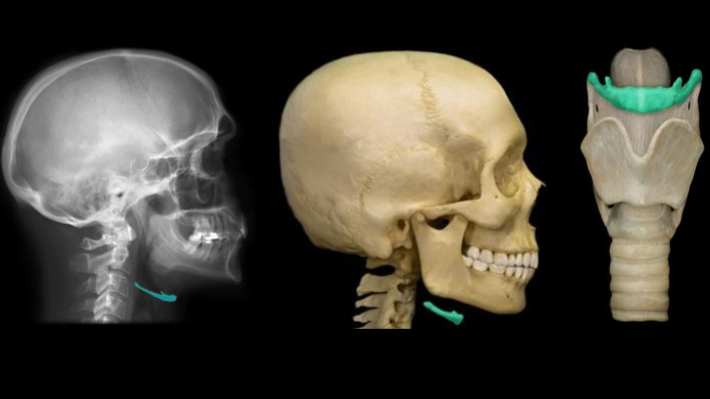

What is the “floating bone under the jaw” that is highlighted in this image called?

hyoid